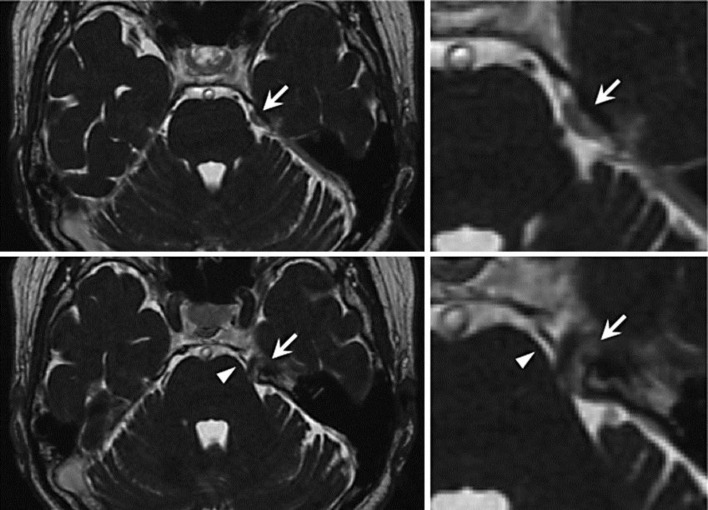

Fig. 2.

Preoperative 3D FIESTA MR images showing an extra-axial tumor (arrow) at the entrance of Meckel's cave that medially compressed and distorted the trigeminal nerve root. The SCA (arrowhead) runs medially proximal to the trigeminal nerve.

The patient's TN ceased completely after the operation. Postoperative 3D FIESTA MR images (fig. 3) confirmed the gross total removal of the tumor and the decompressed and straightened trigeminal nerve root. The pathological diagnosis was meningothelial meningioma (World Health Organization grade 1). The patient was discharged without any neurological deficits.

Postoperative 3D FIESTA MR images showing the gross total removal of the tumor and the decompressed and straightened trigeminal nerve root.